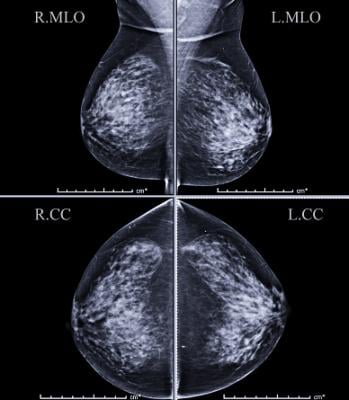

Getty Images

May 19, 2020 — Women with mammographically detected breast lesions that are probably benign should have follow-up surveillance imaging at six months due to the small but not insignificant risk that the lesions are malignant, according to a new study published in the journal Radiology.